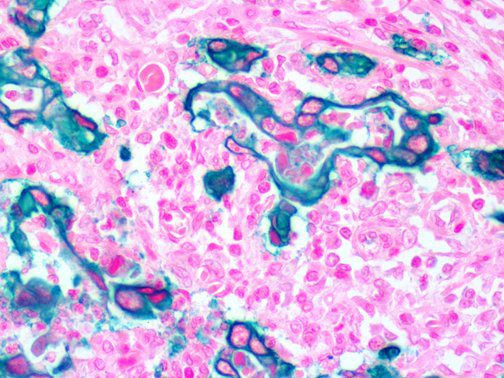

This activation induces inflammatory monocytes to highly express IL-6, starting a localized and then systemic cascade effect that results in hyperproduction of IL-6, which accelerates the inflammatory process. Because IL-6 also increases vascular permeability, excessive levels cause blood vessels to become very leaky. This, along with clotting factors released from vascular endothelial cells, stimulates the coagulation cascade, resulting in microthrombosis (tiny clots), which leads to ischemia and tissue death of the kidney, intestines, heart, liver, brain and extremities.